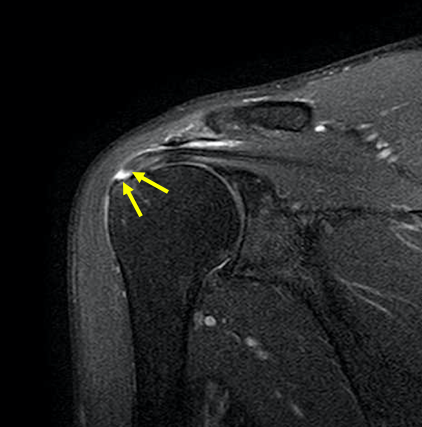

診断は診察所見と超音波検査(a)やMRI検査(b)、単純レントゲン検査の画像所見から行います。

・部分断裂‥腱板の一部が断裂し、上腕骨と連続性が残っているもの

・完全断裂‥腱板が断裂し、上腕骨と連続性がないもの